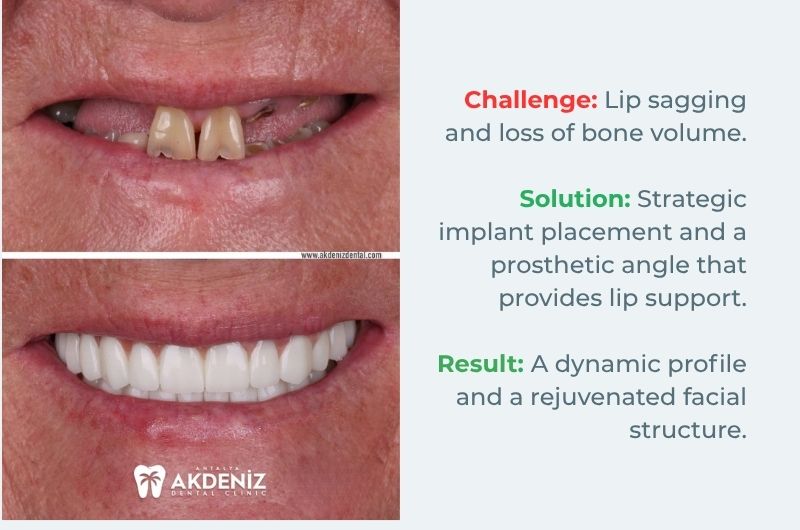

Functional Restoration and Facial Support

Case Analysis 1:

Our primary focus with this patient was to restore the lip structure, which had collapsed inwards due to tooth loss.

Key Detail: Not only the whiteness of the teeth, but also their length and angle were calculated down to the millimetre to support the patient's lip line.

Result: The 'aged face' appearance caused by tooth loss has been replaced by a dynamic and full-bodied profile.